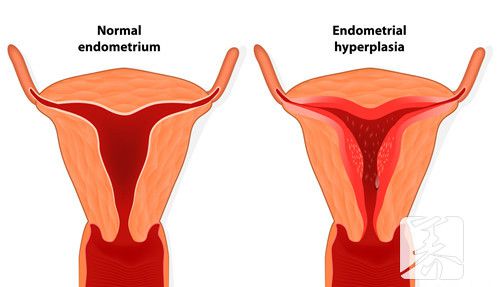

宫腔分离是女人子宫中产生的一个症状表现,许多女士做宫腔内查验的情况下都是显示信息宫腔分离的状况。一些女性检查数据显示宫腔分离2mm,由于不明白医学常识,因此就很困惑,那麼宫腔分离2mm是什么含意?

在为大伙儿答疑解惑这一问题的情况下,首先来跟大伙说说宫腔分离代表什么意思吧。实际上宫腔分离是一种b超检查的专业术语,多表明女士子宫腔有积血积血或残留。有的人可能会觉得沒有做了人流手术,子宫体内就不容易有残余,但大伙儿要了解月经后,子宫壁沒有彻底脱离,也非常容易导致这类状况的。

一切正常状况女士子宫壁是粘在一起的,假如b超显示信息宫腔分离2mm,那麼这就表明子宫腔有积血、血液、浓液等变病,进而造成 宫腔分离。在这类状况下,要融合临床医学开展剖析,如果是绝经后出現宫腔分离,并伴随下腹部疼痛,有些人还会继续出現体温升高的状况,那样的话就可能是子宫腔积脓导致,需要做宫颈扩大实际操作将浓液排出来。

人流手术后宫腔分离2mm,意思是子宫腔两mm的积血沒有所有清除宫腔内,多是孑宫修复欠佳引发,可以吃协助宫缩的药品开展医治。